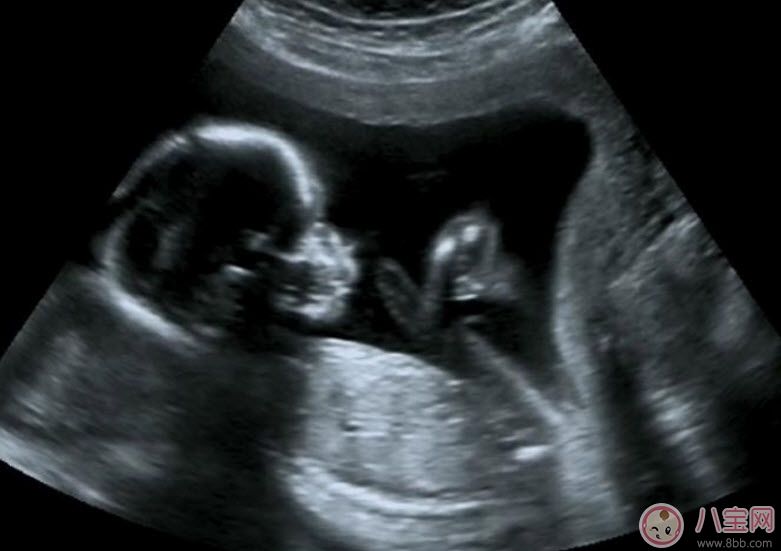

孕期B超作用是什么有什么講究,準(zhǔn)媽媽們都知道在懷孕早期就要去做b超檢查肚子里的寶寶是否健康,那么孕早期B超作用是什么,孕早期B超有哪些講究呢,孕早期孕早期陰道B超對胎兒有影響嗎,應(yīng)該最少做哪幾次b超呢,下面福連學(xué)堂的小編就來說說:孕早期B超作用是什么有什么講究 孕早期陰道B超對胎兒有影響嗎。

B超既可以測量胎兒的各個(gè)部位,如胎頭大小、胎臀長度,也可以用于在早期妊娠來測定胎兒的具體懷孕時(shí)間(醫(yī)學(xué)上叫做孕周),測定胎頭的雙頂徑、頭圍、腹圍及胎兒股骨的長度等,這些數(shù)據(jù)可以判斷胎兒的生長發(fā)育情況。

B超能夠直觀胎兒在母體內(nèi)的活動(dòng)狀況,諸如呼吸情況、胎兒的運(yùn)動(dòng)、整個(gè)身體大的運(yùn)動(dòng)、肢體的運(yùn)動(dòng)、胎兒的吞咽動(dòng)作等等,可以一覽無余。之外,通過觀察胎兒的張力是否良好,可以判斷胎兒在宮內(nèi)是否缺氧或者受到損害,準(zhǔn)確預(yù)報(bào)胎兒安危。